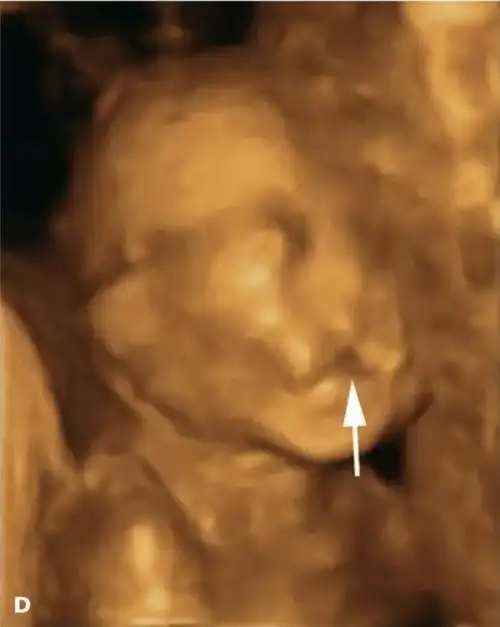

二维三维四维彩超下的唇腭裂胎儿都是怎样的你可能想象不到

妇产科超声多图讲解胎儿唇腭裂的超声诊断

【超声微课堂】胎儿颜面部畸形超声诊断思路:中孕期唇裂和唇腭裂